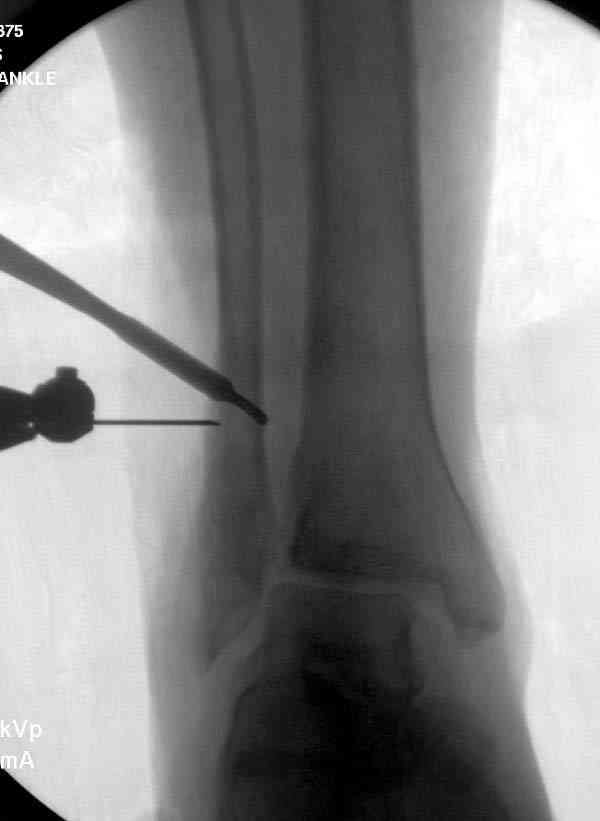

Мне кажется есть все основания попытаться сделать остеосинтез. Боль вследствие нестабильности. Нестабильность вследствие неанатомичного положения дистального отломка малоберцовой кости. Через 1,5 вполне возможно разобщить, репонировать и фиксировать длинный косой перелом наружной лодыжки. Вероятно, одновременно придется делать медиальный доступ для мобилизации внутренней лодыжки. Мы оперируем таких пациентов, функциональные (объем движений) результаты конечно хуже по сравнению с теми кого оперируем в первые 5-10 дней, но вполне удовлетворительные.

Согласен, на предоставленных рентгенограммах все основания для проведения открытого остеосинтеза.

сроки действительно небольшие, но если мы его и возьмем, то пройдет еще минимум неделя, кроме того смущает впечатление сращения н/лодыжки, похоже, что придется не разобщать,а остеотомировать, формирование оссификатов в полости сустава с медиальной стороны, да и сам пациент 1,5 месяца по поводу своей травмы сильно не напрягался